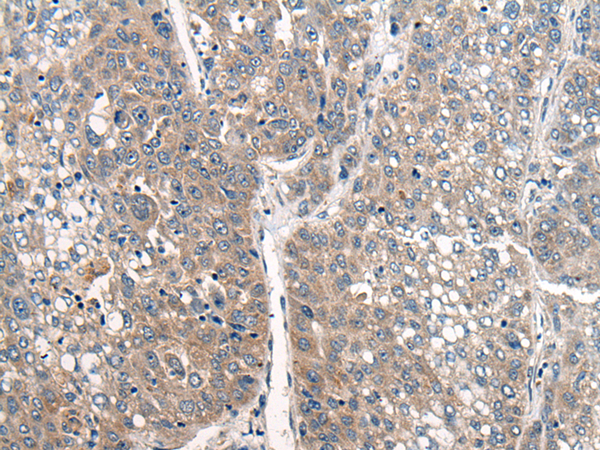

分类: 科研抗体货号: P06279别名:应用: WB,IHC反应种属: Human, Mouse, Rat

分类: 科研抗体货号: P06217别名: NEM7应用: WB,IHC反应种属: Human, Mouse, Rat

分类: 科研抗体货号: P06266别名: NCBP; Sto1; CBP80应用: WB,IHC反应种属: Human, Mouse, Rat

分类: 科研抗体货号: P06210别名:应用: WB,IHC反应种属: Human, Mouse, Rat

分类: 科研抗体货号: P06263别名: CML3; NACED; NAT8-LIKE应用: WB,IHC反应种属: Human, Mouse, Rat

分类: 科研抗体货号: P06205别名: CACC; GOB5; CACC1; CLCRG1; CaCC-1; hCLCA1; hCaCC-1应用: IHC反应种属: Human

分类: 科研抗体货号: P06262别名: DNAS1L2应用: IHC反应种属: Human, Mouse

分类: 科研抗体货号: P06202别名: AMY; CLAC; CLACP; CFEOM5; CLAC-P应用: WB,IHC反应种属: Human, Mouse

分类: 科研抗体货号: P06261别名: DCR2; CD264; TRUNDD; TRAILR4; TRAIL-R4应用: WB,IHC反应种属: Human